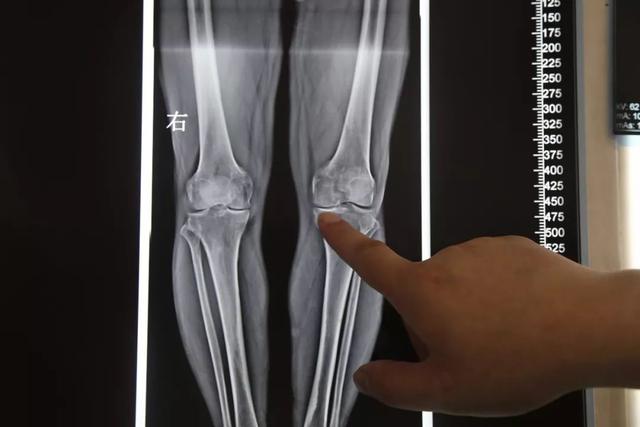

膝关节疼痛又名膝关节退行性关节炎 , 是一种常见的老年人关节疾病 , 会严重影响老年人的生活品质 , 给人的身心健康带来非常大的影响 。 想治疗这类疾病 , 不能心急 , 不要盲目就医吃药 。

为什么会得骨性关节炎?骨关节炎一般都是以50岁以上的老年人为主 , 不过也与患者体重还有膝关节是否受过伤有关 , 还和一些职业有关 , 比如运动员、登山员等 , 还有就是女性的骨性关节炎发病率比男性要早 。

在中青年时期膝关节损伤也是这类疾病的诱因之一 , 还有人在发胖的过程中对膝关节的磨损 , 也是有一定的影响 , 特别是女性 , 会因为内分泌的改变为骨性关节炎埋下隐患 。 还有一些登山爱好者 , 膝关节的损伤更为严重 , 过量的运动对膝关节磨损过大 , 会造成膝关节负重不均匀 , 等到老年时就会出现这类关节疾病 。

病根在年轻时就已经埋下了 , 在老年的时候才会发病 , 所以不要逞着年轻就为所欲为 , 也要为自己的健康着想 。 膝关节的损伤会连带着韧带和半月板 , 甚至软骨的损伤 。 不要因为受伤了去拍个片 , 休息几天消肿了就以为没事了 , 这就是为年老的骨性关节炎埋下了种子 。

膝关节的韧带损伤最容易被忽视 , 等到老年时发病想去根治已经无力回天了 , 就只能实行人工关节置换了 。 研究表明 , 膝关节韧带或半月板损伤10到15年后都会有骨性关节炎 。